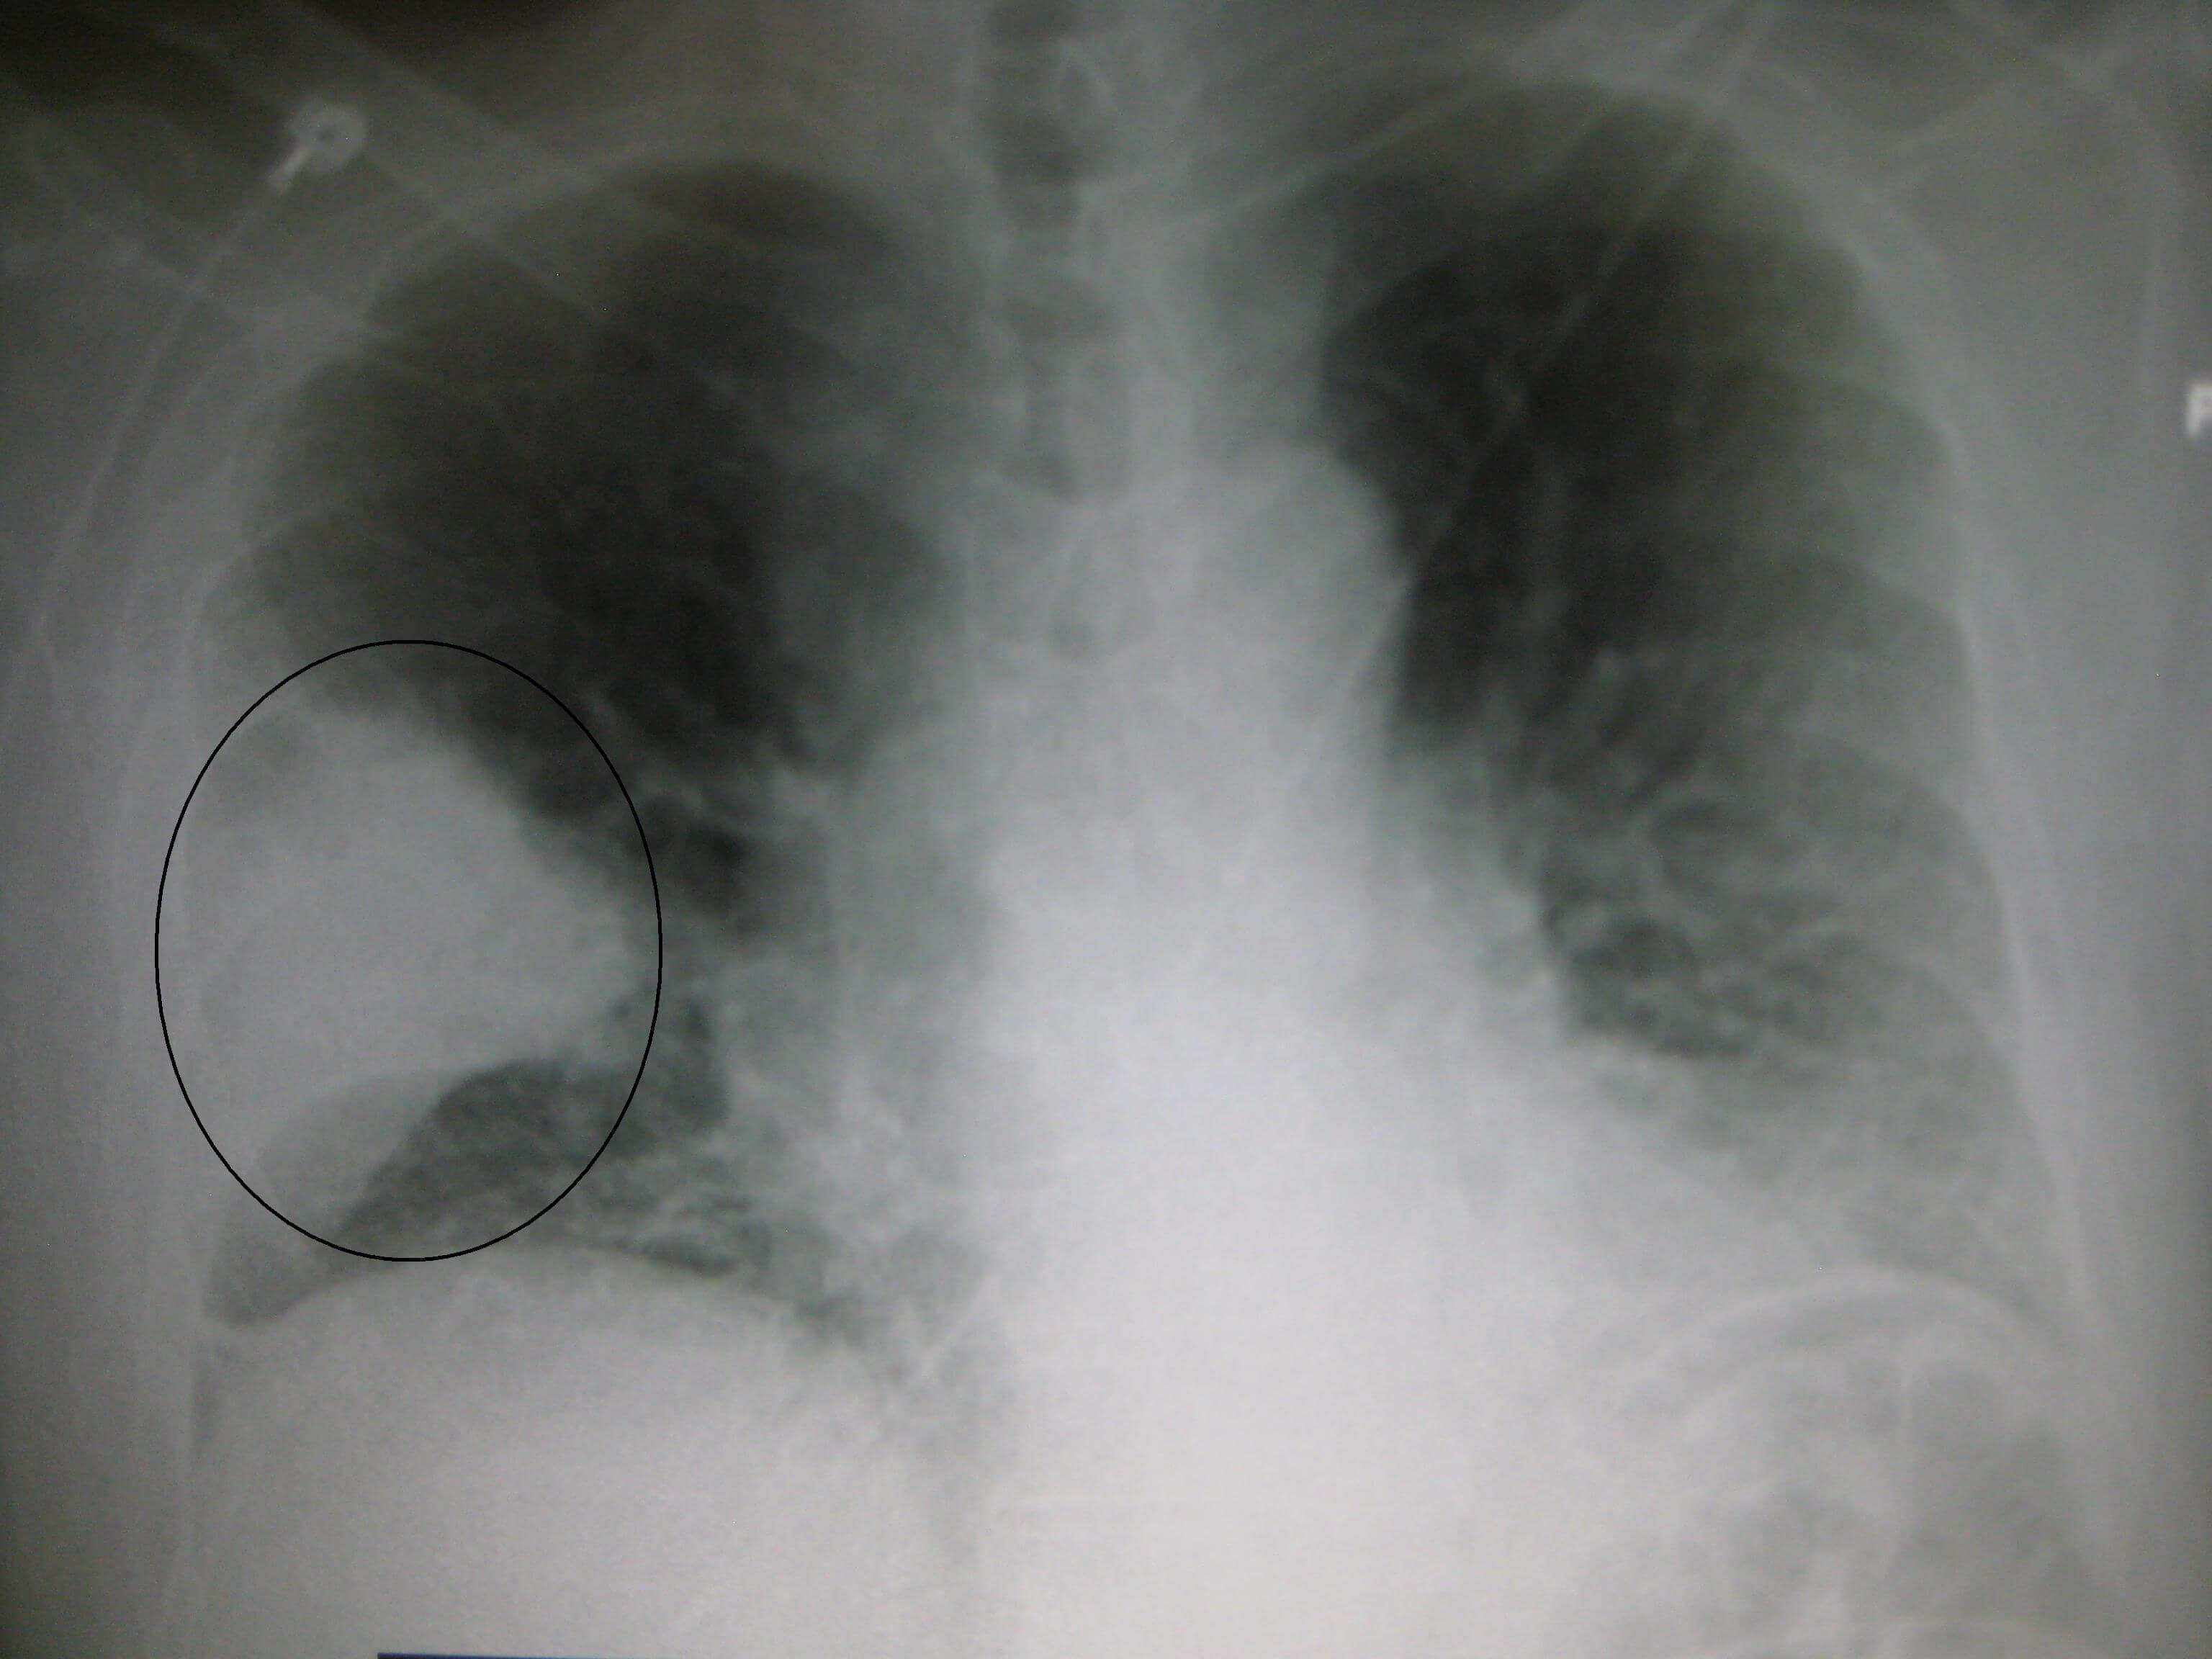

Pneumonia is a bacterial, viral, or fungal infection of one or both sides of the lungs that causes the air sacs, or alveoli, of the lungs to fill up with fluid or pus.

Symptoms can be mild or severe and may include a cough with phlegm (a slimy substance), fever, chills, and trouble breathing. Many factors affect how serious pneumonia is, such as the type of germ causing the lung infection, your age, and your overall health. Pneumonia tends to be more serious for children under the age of five, adults over the age of 65, people with certain conditions such as heart failure, diabetes, or COPD (chronic obstructive pulmonary disease), or people who have weak immune systems due to HIV/AIDS, chemotherapy (a treatment for cancer), or organ or blood and marrow stem cell transplant procedures.